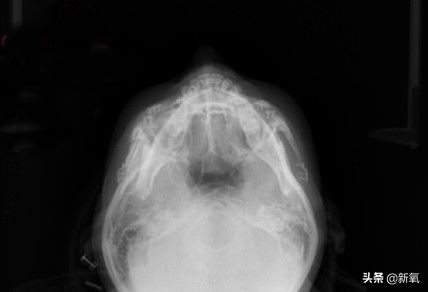

从头顶上来看,经过上次颧骨内推之后,她的颧骨两侧高低不一样,有些不对称,所以这次进行了修复矫正。